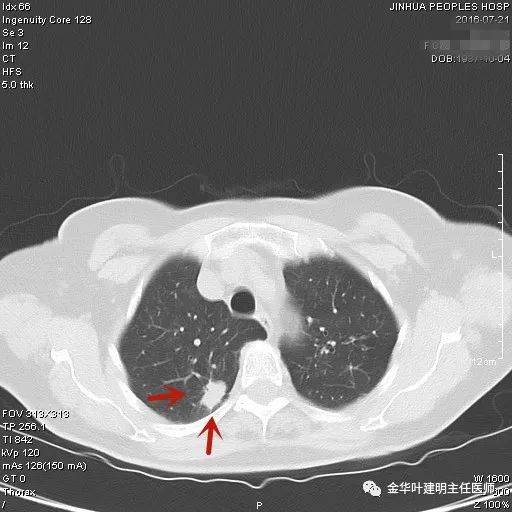

上图是纤维增生,但我们看病灶有明显的叶间胸膜牵拉,虽然力度弱,但这么小的病灶能指望它有多少力度呢?恶性还是不能除外的。